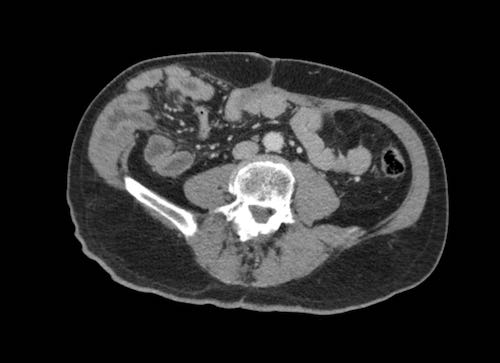

Ca lâm sàng 1

Cuộn qua các lát cắt.

Bạn có thể phát hiện tất cả các tổn thương cấy ghép phúc mạc không?

Bệnh nhân này đã được phẫu thuật và toàn bộ phúc mạc được ghi nhận phủ kín bởi các tổn thương u dạng kê.

Ca lâm sàng 2